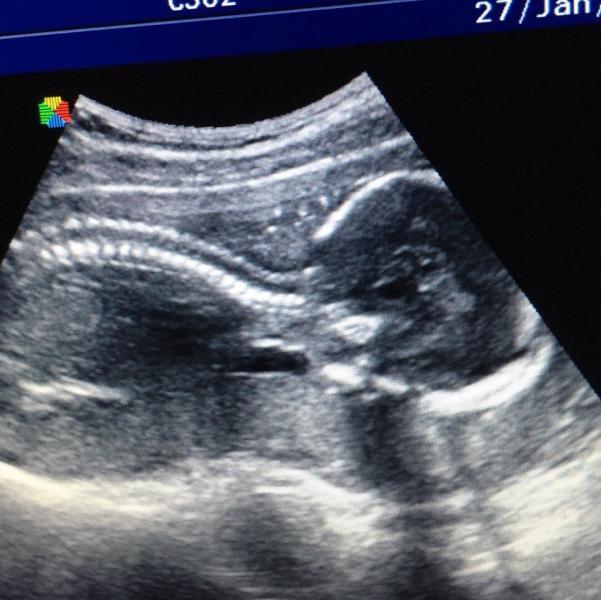

Были вчера на УЗИ - 20 недель)

Второй скрининг)

🔺весим 350г

🔺растем хорошо, все в норме 😊

🔺подтвердили девочку и показали папе))

🔺лежит вниз головой, но это так вышло, пока ещё свобода и крутится как хочет)

🔺плацента низковато, на 24мм от "входа", а должна быть 40мм. Сказала - ещё поднимется, она имеет свойство "прыгать".

🔺забыла принести мочу, дали сдать прям там, сразу проверили, в ней лейкоциты 😳. Сказали в пт утреннюю занести, Т к прием был в 19:00, скорее всего попало туда что-то из других ...